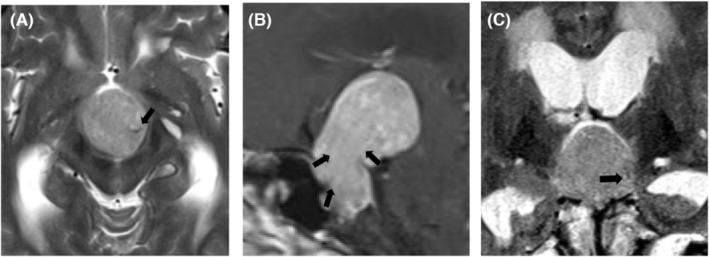

To investigate the blood supply characteristics and surgical significance of pituitary neuroendocrine tumors with vascular flow void signal in tumors. The clinical data of one case of giant pituitary neuroendocrine tumor with vascular flow void signal were reported, and the related literature was reviewed. In this case of pituitary neuroendocrine tumor, the blood sinus from the superior pituitary artery was seen in the left rear of the tumor before the first operation, showing irregular low signal. Subsequently, the tumor recurred 46 mm high, grew upwards, and had no cystic degeneration. The blood vessels that showed flow voids signal in magnetic resonance imaging originated from the inferior pituitary artery. The tumor was removed through the frontal lobe through the lateral ventricle approach, and desirable results were obtained. Vascular flow void signals in giant pituitary neuroendocrine tumors are rare, which suggests a sufficient and rich arterial blood supply. Arterial blood supply from below such tumors should be properly handled during the operation.

探讨肿瘤内有血管流空信号的垂体神经内分泌肿瘤的血供特点及手术意义。报道1例有血管流空信号的巨大垂体神经内分泌肿瘤的临床资料,并复习相关文献。该例垂体神经内分泌肿瘤在首次手术前于肿瘤左后方可见来自垂体上动脉的血窦,呈不规则低信号。随后肿瘤复发,高46 mm,向上生长,无囊性变。磁共振成像显示流空信号的血管起源于垂体下动脉。经侧脑室额叶入路切除肿瘤,效果满意。巨大垂体神经内分泌肿瘤中的血管流空信号少见,提示动脉血供充足且丰富。手术中应妥善处理此类肿瘤下方的动脉血供。